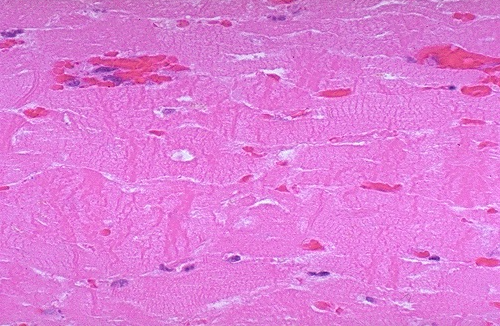

- Earliest change histologically seen with acute myocardial infarction in the first day is contraction band necrosis

- Myocardial fibers are beginning to lose cross striations and the nuclei are not clearly visible in most of the cells seen here

- Note the many irregular darker pink wavy contraction bands extending across the fibers